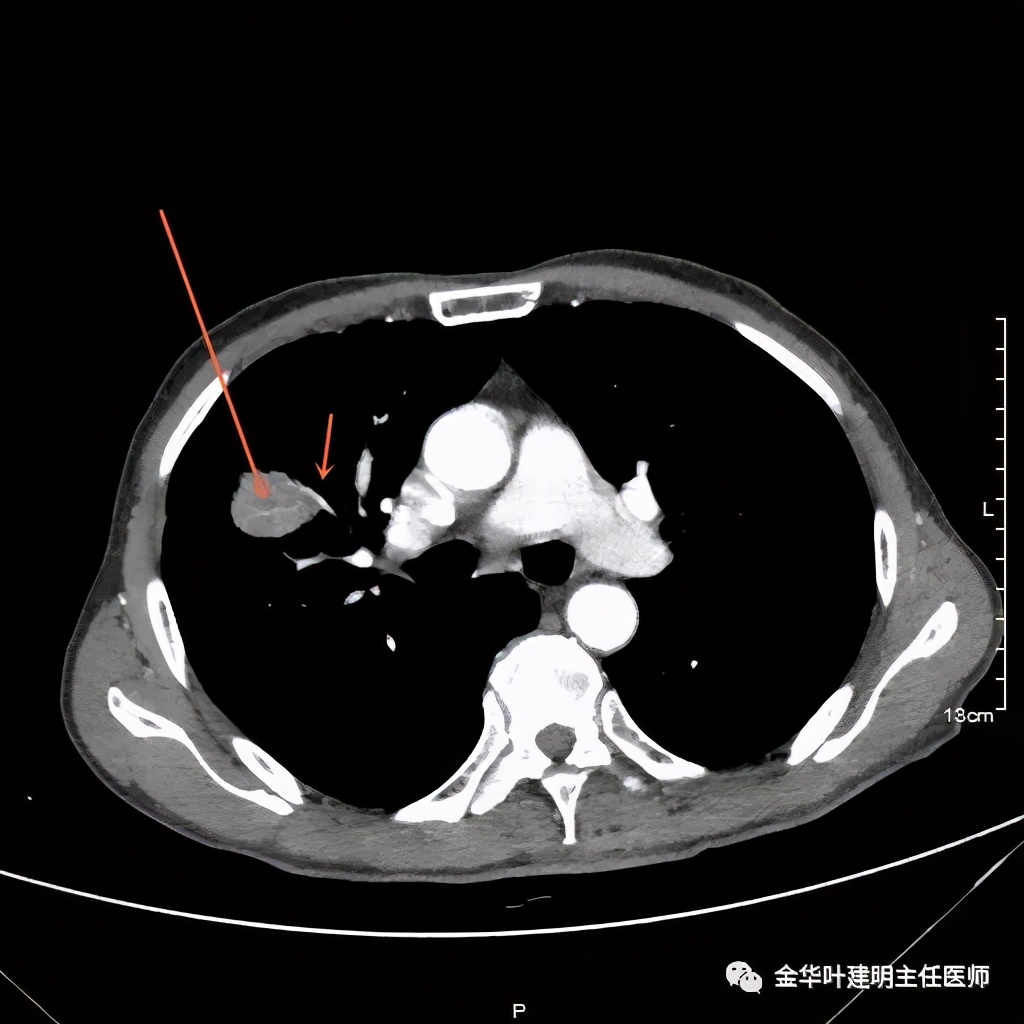

上图示纵隔窗病灶有膨胀性,内部有强化较明显的条索状(新生血管?)

上图示纵隔窗病灶表面欠平整,中间有小空洞,密度不均,局部似有坏死(空洞旁边)

桔色箭头示病灶周围血管征明显,有较粗的血管进入病灶,较细的也有

上图箭头示强化的血管与病灶关系密切,而且有被病灶侵犯影响的感觉,部分界限是不清楚的

上图示病灶内部有条索状的强化影,考虑是病灶内的新生血管可能性大

上图示病灶强化不等,表现不平,中间有空洞,空洞旁边有偏低密度区(坏死?)

上图示病灶膨胀分叶,表面不平,像个土豆

上图示病灶密度不均,有偏低密度的区域

上图黄色箭头示空洞形成,病灶表面不平